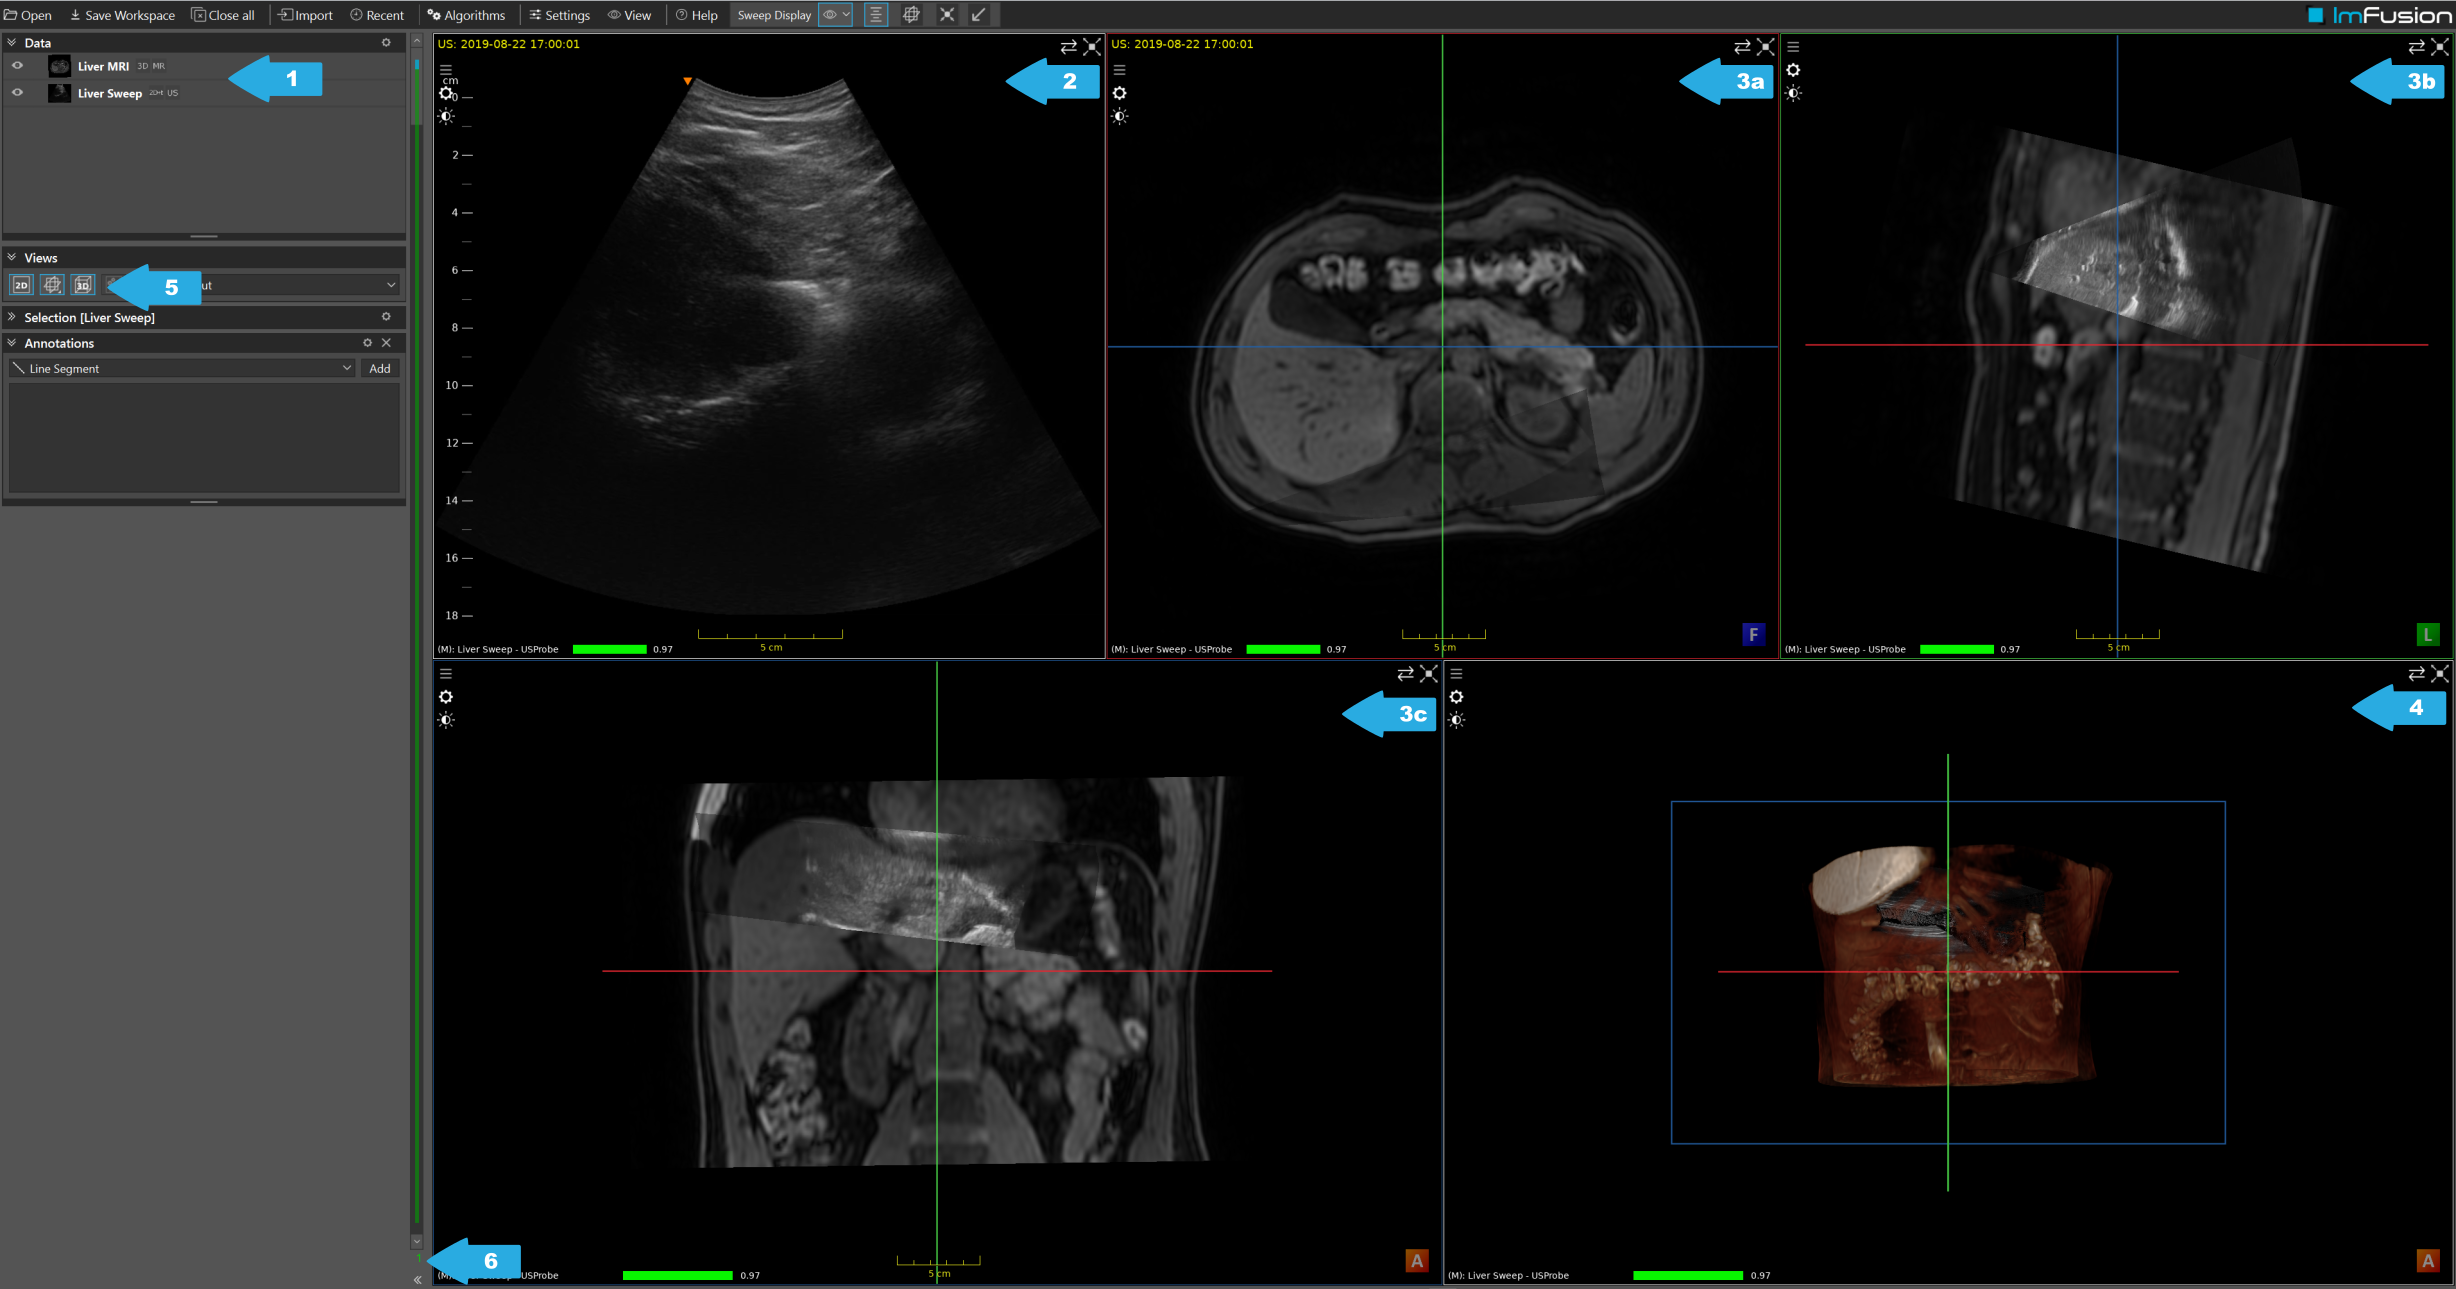

The ImFusion Suite after loading the data.

After loading the data, we will see a list of loaded data (1), a 2D view of the ultrasound sweep (2), three 2D Multiplanar Reconstruction (MPR) views (3), and a 3D view of the MR volume and the sweep (4). We can activate or deactivate views via the Views controller (5). The number in (6) tells you which frame of the ultrasound sweep is currently displayed.